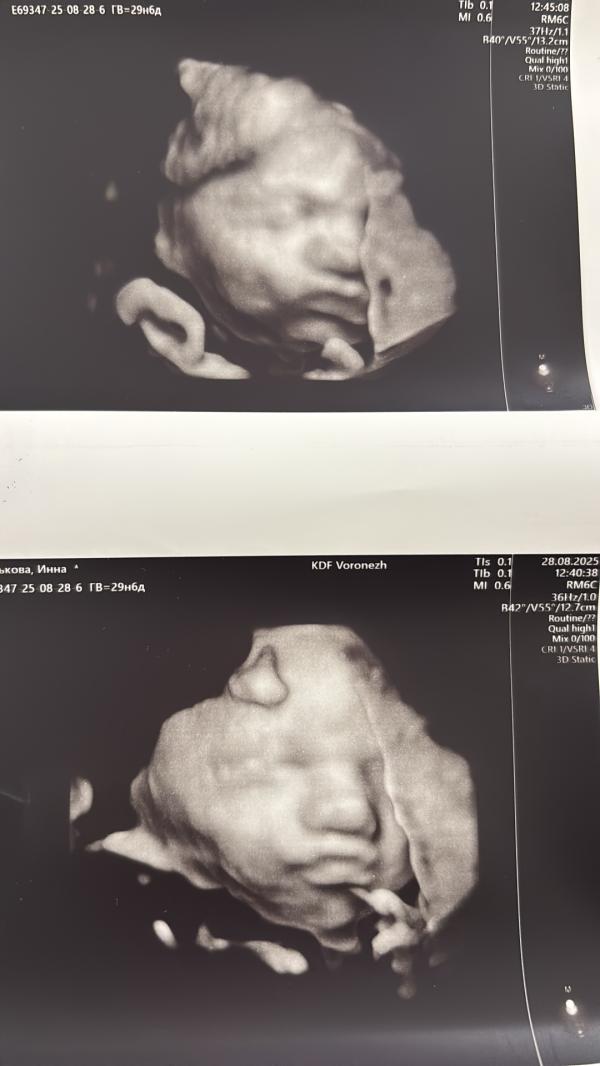

Сходила на узи- срок 29,6! По узи всё гуд 👍! Соответствует сроку

Вес 1540+-200гр.

Сделали фоточку на память!

Серьезная дама у меня😁